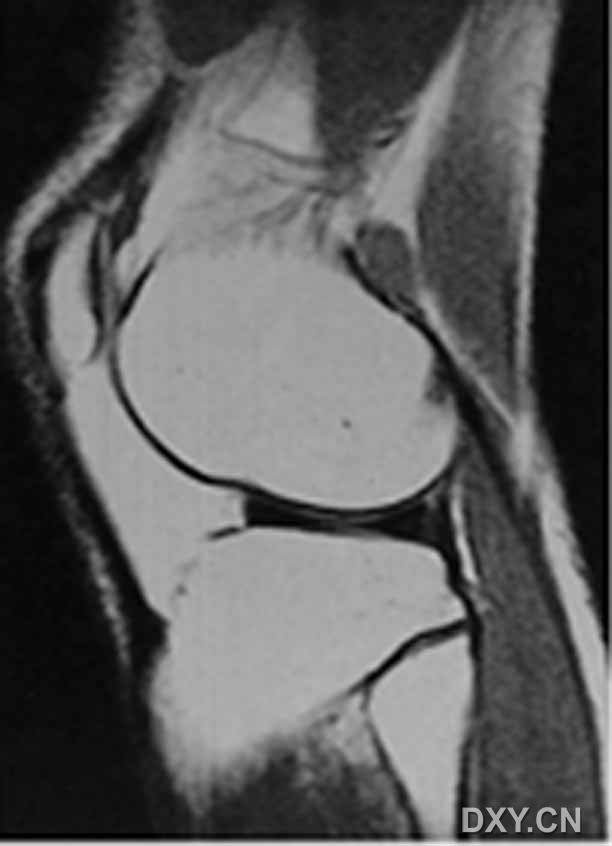

| 双前、后交叉韧带征

|